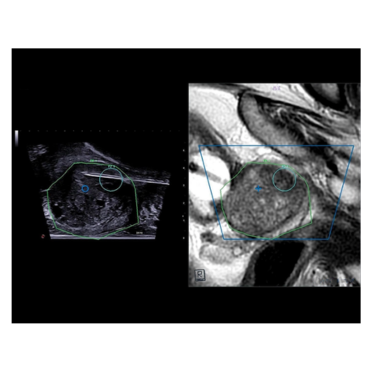

Biopsies de la prostate par voie trans-périnéale en fusion écho-IRM (ESAOTE UROFUSION) :

Depuis juillet 2024, la Clinique Belledonne dispose du dispositif ESAOTE UROFUSION, permettant la réalisation de biopsies ciblées de la prostate par voie transpérinéale. Cette méthode offre des bénéfices significatifs en termes de précision, de confort pour le patient et de réduction des risques associés.

Grâce à l’imagerie IRM, il est désormais possible d'identifier avec plus de fiabilité les patients nécessitant une biopsie de la prostate. En cas de dosage du PSA élevé ou de palpation anormale lors d’un toucher rectal, l’IRM permet de localiser les zones suspectes. Lorsqu'aucune anomalie n’est détectée à l'IRM, une biopsie peut être évitée dans 1 cas sur 4, évitant ainsi des examens inutiles.

Si une zone suspecte est identifiée, la technologie de fusion d’images IRM-échographie permet de guider les biopsies avec une grande précision. Cette approche réduit le nombre de prélèvements nécessaires tout en ciblant directement les zones à risque, ce qui :